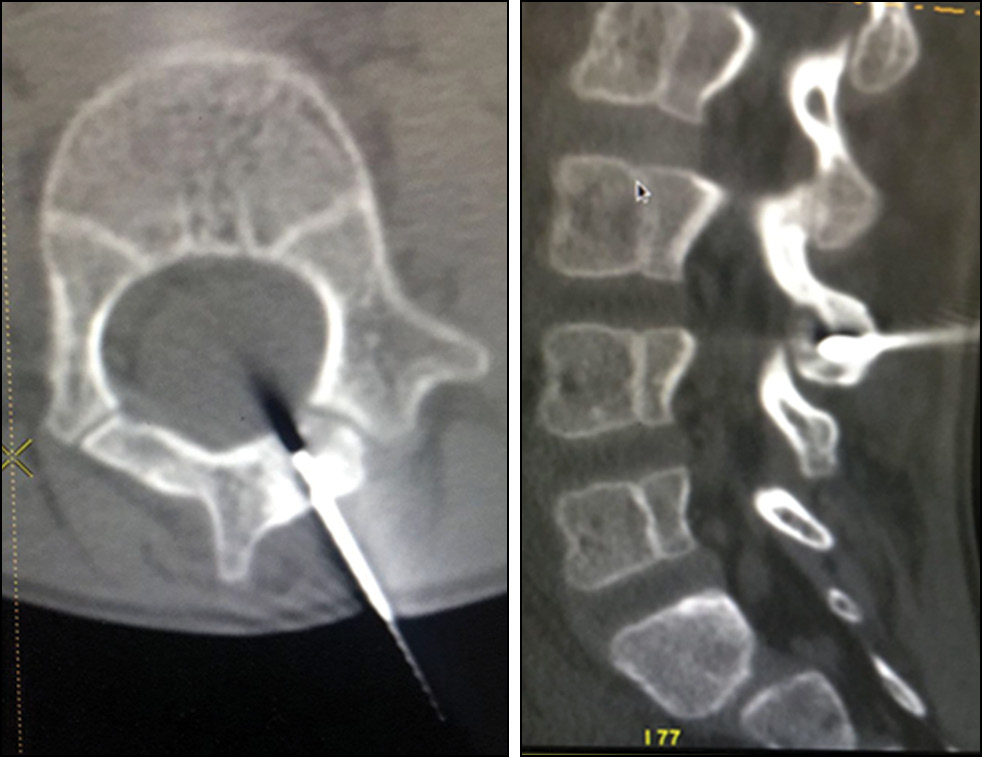

В нашей выборке в трёх случаях при локализации в грудном отделе проводилась резекция новообразования через торакотомный доступ. С появлением видеоэндоскопического контроля резекция опухоли в подобных случаях проводилась нами с применением этого метода. Данным методом выполнено удаление двух опухолей (рис. 2).

Рис. 2. Резекция остеоид-остеомы Тh6 позвонка под видеоэндоскопическим контролем.

Fig. 2. Videoendoscopy-guided resection of a Th6 vertebral osteoid osteoma

Проведение видеоэндоскопии существенно расширяет арсенал хирурга, предоставляя ряд существенных преимуществ. Основное достоинство данного метода — его малая инвазивность, а также возможность формирования более удобного и точного угла атаки, что является критически важным для экономной резекции новообразования [7, 11]. В то же время видеоэндоскопия имеет ряд недостатков, таких как более сложная оценка ревизии дна пострезекционного дефекта, который прилегает к содержимому позвоночного канала. Также может увеличиваться время операции в силу недостаточного опыта применения данной технологии [7], однако этот недостаток не является лимитирующим ввиду редкости такой локализации и самой патологии.